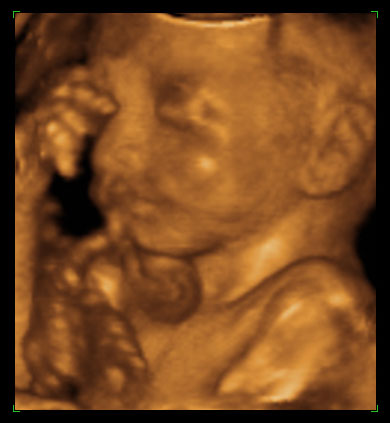

ултразвучни приказ бебе 24. недеље трудноће (2)